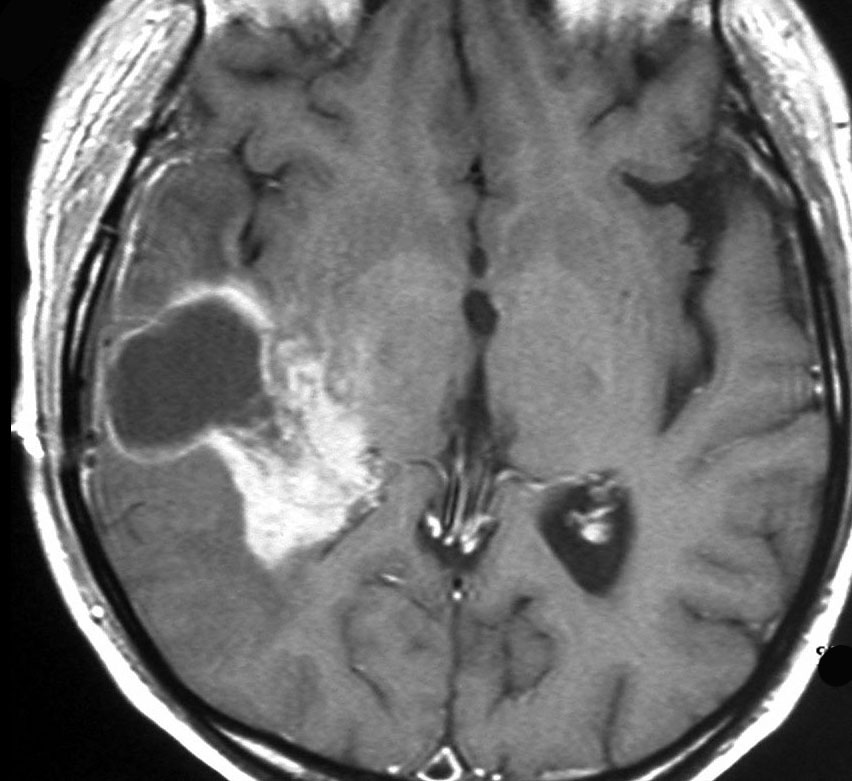

放射線誘発膠芽腫(グリオブラストーマ)

松果体のジャーミノーマのために,19歳の時に全脳照射30グレイと松果体局所照射20グレイを受けました。これは28歳の時に発生した右側頭葉の膠芽腫です。この部分には30グレイしか入っていないのですが,2.5グレイという大きな1日線量が用いられていました。またslit-beam rotationという1990年代初頭に用いられた照射方がされています。同じ線量であっても二次ガンを招きやすい照射法というのがあるのかもしれません。